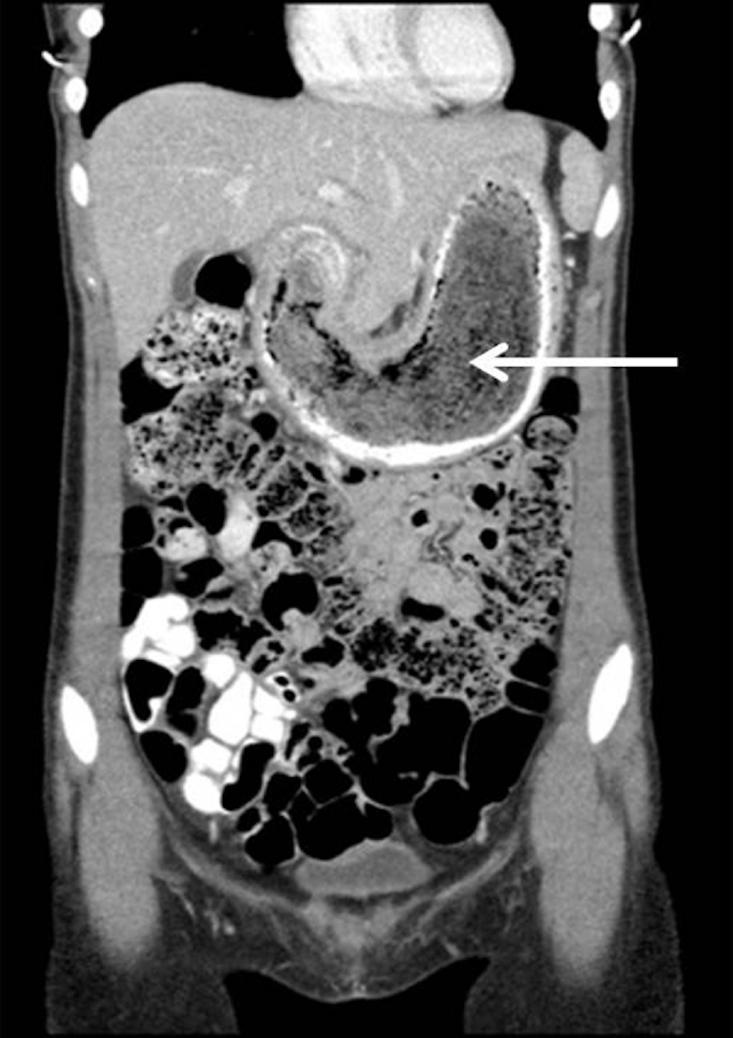

It can seem odd that, for all the stones removed from the innards of herbivores over the centuries, the first documented postmortem diagnosis of bezoar in a person wasn’t made until the mid-1800s. A bezoar’s obstruction of the normal flow of digesting food can result in damage to the walls of the digestive tract, resulting in ulcers, bleeding, and, as a worst-case scenario, perforation of the intestinal wall and subsequent infection of the abdominal cavity with poop bacteria. As Gardiner put it: “Consider that what was once a magical stone endowed with life-giving properties is now a cause for surgical intervention and a portent of evil.”

Doctors have drummed up a range of ways to rid people of their bezoars. The most exciting and least invasive option is to use high-energy shock waves to break it apart from outside of the body. Alternatively, it may be necessary to insert an endoscope and disintegrate the bezoar with a jet of water or a laser-ignited mini-explosive. A third approach is to dissolve, or at least soften and mobilize, the bezoar by using a scope to directly inject a substance capable of breaking down materials other than the walls of one’s stomach and intestine. Depending on the composition of the bezoar, these substances may include Coca-Cola, protein-degrading enzymes found in papayas and pineapples, cellulase, and N-acetylcysteine. A fourth approach is laparoscopic surgery, which means making a small cut in the abdomen and inserting a tool to remove the bezoar. Finally, the nuclear option is to open things right up and take it out. It’s recommended if the bezoar is too big for the other approaches to work properly, or if life-threatening intestinal obstruction or perforation occurs. But in this scenario, surgeons need to be especially alert. Under exceptional circumstances, bezoars may explode during surgery! As one 2005 report warned: “Beware of the flaming hairball.”